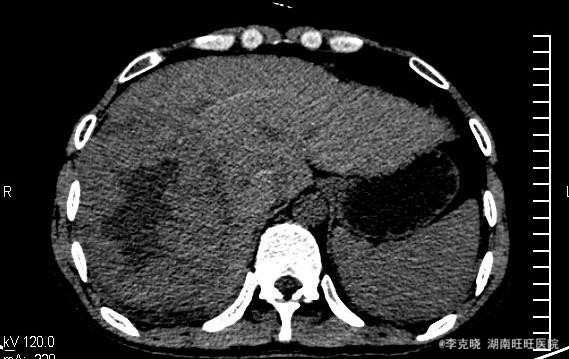

四测正常,皮肤巩膜无黄染,心肺部听诊未闻及杂音。腹平坦,未见胃肠型及蠕动波,无腹壁静脉曲张,全腹柔软,右侧肋缘深压痛,无反跳痛,肝肾无叩痛,肝肺浊音界清晰,肠鸣音正常。四肢活动自如,无水肿。 辅助检查提示:血常规、凝血常规基本正常,谷丙转氨酶278u/l,谷草转氨酶326u/l,AFP大于20000。上腹部CT增强提示:右肝巨大占位,平扫期呈低密度,动脉扫描时强化明显,静脉延迟象呈现低密度,结合病史考虑原发性肝癌可能,建议结合临床。

诊断:原发性肝癌(右肝巨块型)。治疗:考虑到患者的经济状况,结合肿瘤的影像学特点,经与患者充分沟通“以手术治疗为主的肝癌综合治疗思路”,最终患者选择先行TACE治疗。治疗后住院9天复查肝功能,转氨酶有下降趋势时,给予患者出院。一个半月后返院复查,转氨酶稍高,肿瘤内部碘油沉积满意,未见新生血管生成和新生病灶,建议患者继续观察、随访。